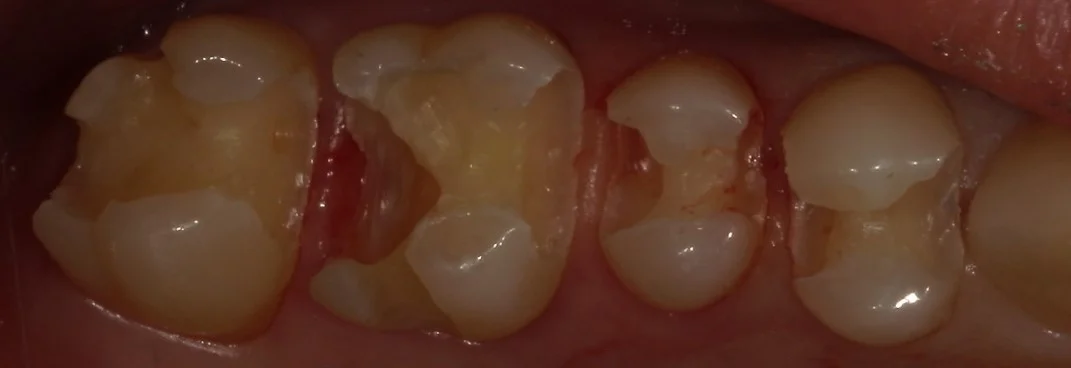

さて、金属を外したのがこちらです。

歯の周りで黒くなっている部分のほとんどは虫歯ではなくセメントが黒く着色しているだけの状態ですが・・・

これは要はセメント部分が劣化しているから起こっているのです。

その為、その劣化した部分から内面に向かって虫歯が入り込んでいる場合が多々あります。

今回のこのお写真でも、非常に大きく虫歯が入り込んでいました。

虫歯を取りきったのがこちらの写真です。

綺麗な歯の色が露出したと思います。

ここまで大きく虫歯になっていたとしても、実は症状とかは特に出ないんです。